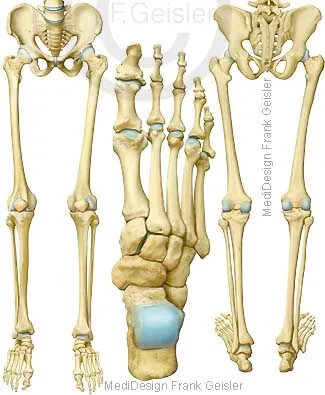

Wirbelknochen der Wirbelsäule; Ansichten Becken mit untere Extremitäten, Draufsicht Fußknochen

Im mittleren Lebensalter besteht das Skelett eines Menschen aus mehr als 200 einzelnen Knochen. Die Wirbelsäule (Columna vertebralis) setzt sich aus 24 Wirbeln (Vertebrae), dem Kreuzbein (Os sacrum) und dem Steißbein (Os coccygis) zusammen. Das Kreuzbein bildet sich durch die Verschmelzung von fünf einzelnen Wirbeln, das Steißbein entsteht aus zwei bis sieben Wirbelrudimenten. Zum Stammskelett gehören außerdem das Brustbein (Sternum) und die zwölf Rippenpaare (Costae). Das Kopfskelett, der Schädel (Cranium), besteht insgesamt aus 33 einzelnen Knochen, davon werden 15 dem Hirnschädel und 18 dem Gesichtsschädel zugeordnet. Zum Schultergürtel gehören jeweils rechts und links das Schlüsselbein (Clavicula) und das Schulterblatt (Scapula). Die obere Extremität wird gebildet vom Oberarmbein (Humerus), der Speiche (Radius), der Elle (Ulna), acht Handwurzelknochen (Ossa carpi), fünf Mittelhandknochen (Ossa metacarpalia I-V) und vierzehn Fingerknochen (Ossa digitorum manus).

Zum Beckengürtel gehört das Hüftbein (Os coxae) und zum Skelett einer freien unteren Extremität das Oberschenkelbein (Femur), die Kniescheibe (Patella), das Wadenbein (Fibula), das Schienbein (Tibia), sieben Fußwurzelknochen (Ossa tarsi), fünf Mittelfußknochen (Ossa metatarsalia I-V) und vierzehn Zehenknochen (Ossa digitorum pedis).